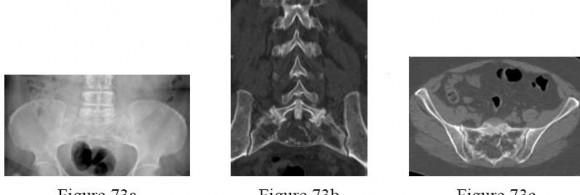

Question 73

A 35-year-old unrestrained passenger is involved in a motor vehicle collision. Radiographs demonstrate a unilateral facet dislocation in the cervical spine.

What is the primary mechanism of injury leading to this specific pathology?

Explanation